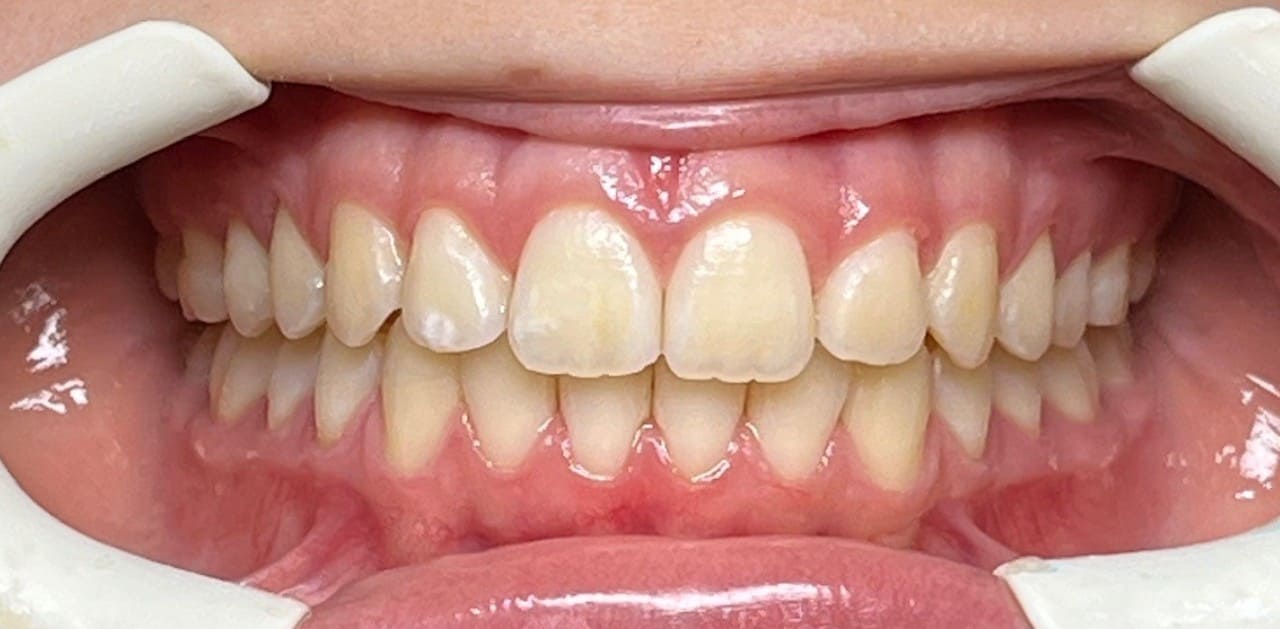

Initial

Final

Results achieved

- Class I relationship achieved

- Functional canine guidance on both sides

- Normal overjet and overbite achieved

- Deepbite improved

- Overjet improved

- Midlines coincident

- Curve of Spee leveled

- Arches aligned and coordinated

- Aesthetic smile line was achieved

- All treatment goals were achieved case